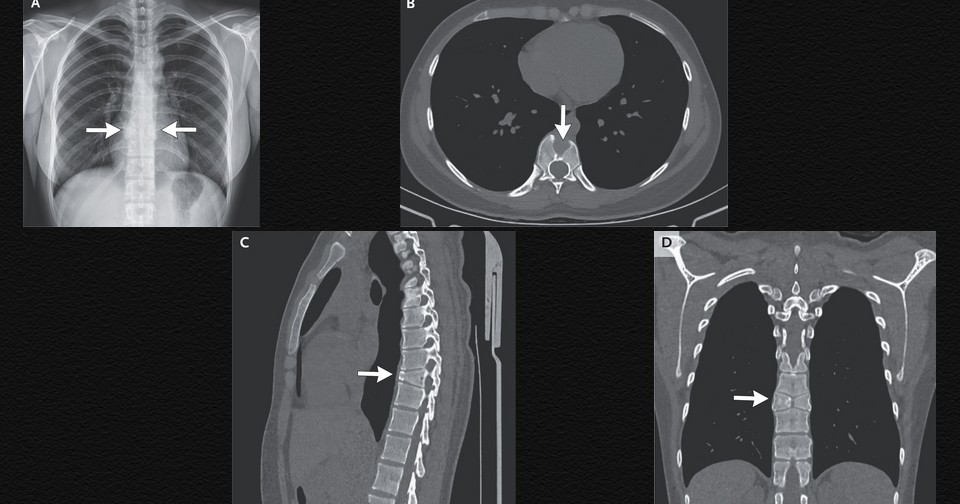

В китайскую пульмонологическую клинику обратилась 21-летняя женщина с жалобами на кашель и першение в горле в течение недели. При осмотре определялось только умеренное покраснение глотки. Болей в спине в анамнезе она не отмечала. На рентгенограмме органов грудной клетки у пациентки визуализировались нормальные легкие и два полупозвонка на месте тела девятого грудного позвонка. Ее направили на компьютерную томографию, которая выявила сагиттальное расщепление, переднюю клиновидную деформацию и симметричные треугольные полупозвонки на уровне девятого грудного позвонка. Шуай Дин (Shuai Ding) и Синь Пань (Xin Pan) из Четвертой аффилированной больницы Китайского медицинского университета в Шэньяне поделились этим случаем в The New England Journal of Medicine.

На основании данных радиографической находки женщине поставили диагноз бабочковидного позвонка — редкой врожденной аномалии, обусловленной отсутствием слияния двух латеральных центров окостенения позвонка в процессе внутриутробного развития. Этот дефект может быть изолированным, как в данном случае, или сочетаться с другими аномалиями развития. Дополнительное обследование профильными специалистами подтвердило доброкачественный характер заболевания и отсутствие потребности в специальном лечении. Кашель и першение в горле сочли проявлениями неосложненной инфекции верхних дыхательных путей и назначили поддерживающую терапию.